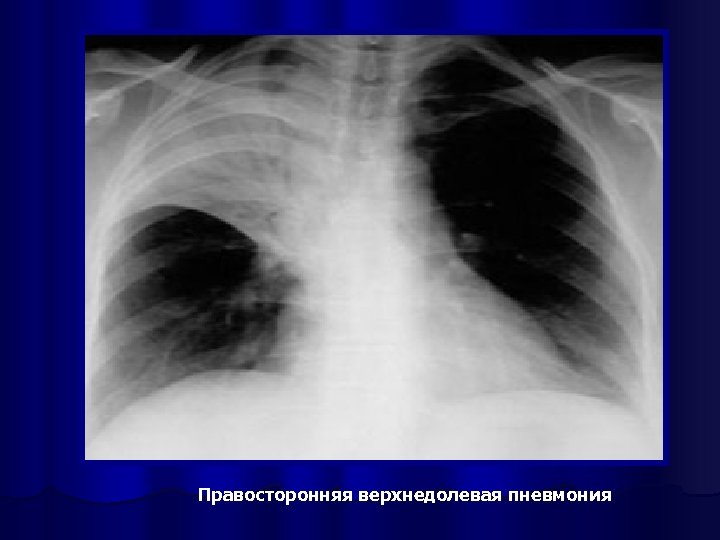

Правосторонняя верхнедолевая пневмония

Рентгенография органов грудной клетки l обязательный метод исследования при пневмонии, l позволяет визуализировать пневмонический инфильтрат, l оценить динамику процесса, l распространённость инфильтрации, наличие плеврального выпота, признаков деструкции лёгочной ткани отражают тяжесть заболевания и определяют тактику лечения.

Рентгенологическое исследование проводится в начале заболевания и не ранее чем через 14 дней после начала АБТ; может быть выполнено и в более ранние сроки при возникновении осложнений или существенном изменении клинической картины заболевания l в практической работе полноформатная пленочная рентгенография часто заменяется крупнокадровой флюорографией или цифровой флюорографией, которая в этих случаях выполняется в аналогичных проекциях l в типичных случаях ВБП критерий диагноза - обнаружение очагово-инфильтративных или интерстициальных изменений в легких l

Рентгенологическая картина ВП l Основной рентгенологический признак ВП - локальное снижение воздушности легочной ткани (инфильтрация) за счет накопления воспалительного экссудата в респираторных отделах. l Рентгенологическая и КТ картина ВП определяется типом инфильтрации легочной ткани и стадией воспалительного процесса.